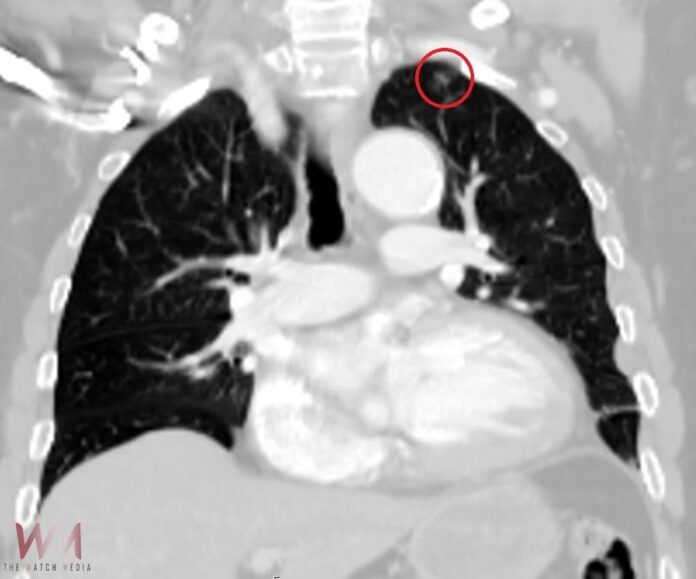

切除可疑肺病灶《紅圈處》後,病理報告證實為最早期的第一期肺腺癌。(圖/光田綜合醫院提供)

進一步發現可疑病灶後,陳紀寰醫師立即與患者及家屬溝通,說明目前的手術計畫將進入胸腔處理骨折與積血,同時也建議利用這次機會,直接切除可疑肺病灶,爭取最佳治療時機。手術順利完成後,病理報告證實為「肺腺癌」。所幸是顆小於1公分的早期腫瘤。陳紀寰醫師指出,該名患者屬於肺癌最早期的第一期,是所有肺癌分期中最輕微、預後最好的階段,不僅幾乎無症狀,治癒率極高。也正因為發現得早,處理及時,術後無需接受化療或放療,目前恢復良好,僅需定期追蹤觀察。